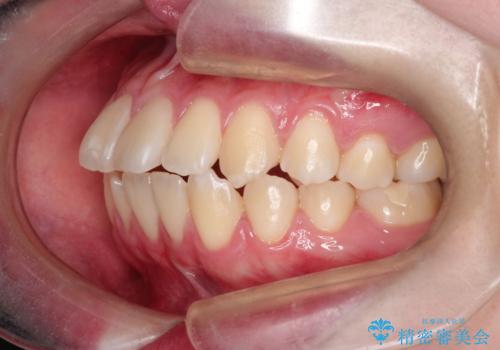

【インビザライン】歯を抜かずにできるだけ前歯を下げたい

- 前歯の前突を主訴に来院されました。

インビザライン を用いて、歯並びの改善を行うことができました。